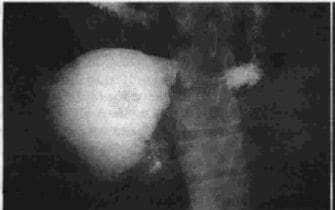

Figura 3. Estudio radiológico, hernia hiatal.

Figura 4. Estenosis por úlcera pilórica.

Figura 5. Estenosis boca anastomótica, control B. I.

Figura 6. Estenosis y dilatación Asa de Henley.[/enc_su_column]

Figura 7. Estudio HIDA, reflujo entero-gástrico.

Figura 8. Estudio endoscópico : gastritis atrófica.

Figura 9. Experimentos de Delaney, tubos gástricos expuestos

Figura 10. Estudio histológico: gastritis superficial a la acción de diferentes jugos.[/enc_su_column]